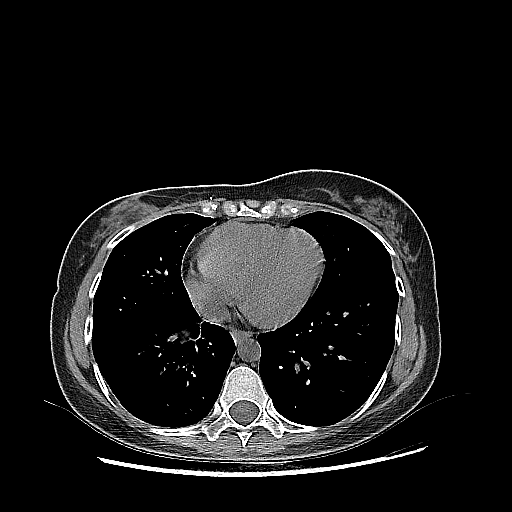

Original VENOUS CT scan

Full window (WL 1023.5, WW 4095 β†’ Low βˆ’1024, High +3071)

Actual HU range: [-160.0, 240.0]